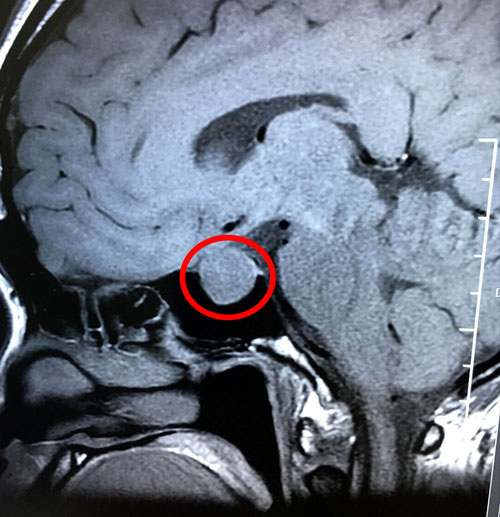

术前影像:垂体大腺瘤,超蝶鞍生长

在医院神经外科潘仁龙主任的安排下,郑钰玲又做了检查,发现垂体瘤又长大了,大小是1.9*1.5*1.7公分,而且超蝶鞍生长。完善血尿常规,生化,凝血,心电,彩超等各项检查之后,未发现手术禁忌。潘仁龙主任和李士其教授又进行了会诊和术前讨论。